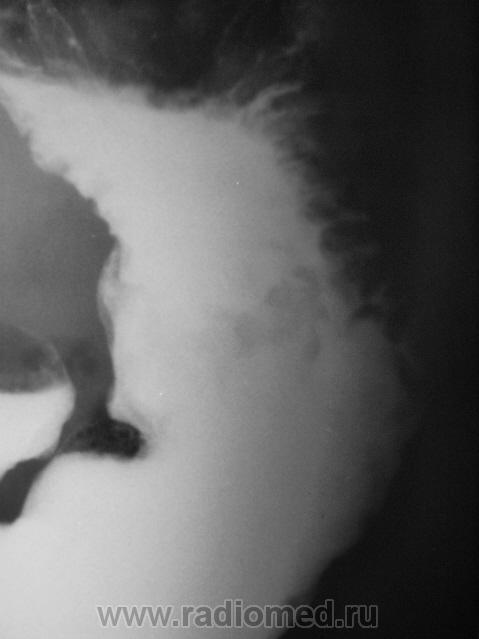

Пациент, который длительное время находился на диспансерном учете, как "язвенный больной", в последние годы не обследовался. Отмечает, что болей не ощущает, но очень резко похудел за последние два года.

нехорошая язва, уже может быть и инфильтративно-язвенные рак, биопсию надо делать

Ригидность контуров всего тела желудка, центральный дефект наполнения в теле, изьязвление по малой кривизне, кисетообразная деформация всего желудка - убедительные признаки обширного опухолевого поражения.